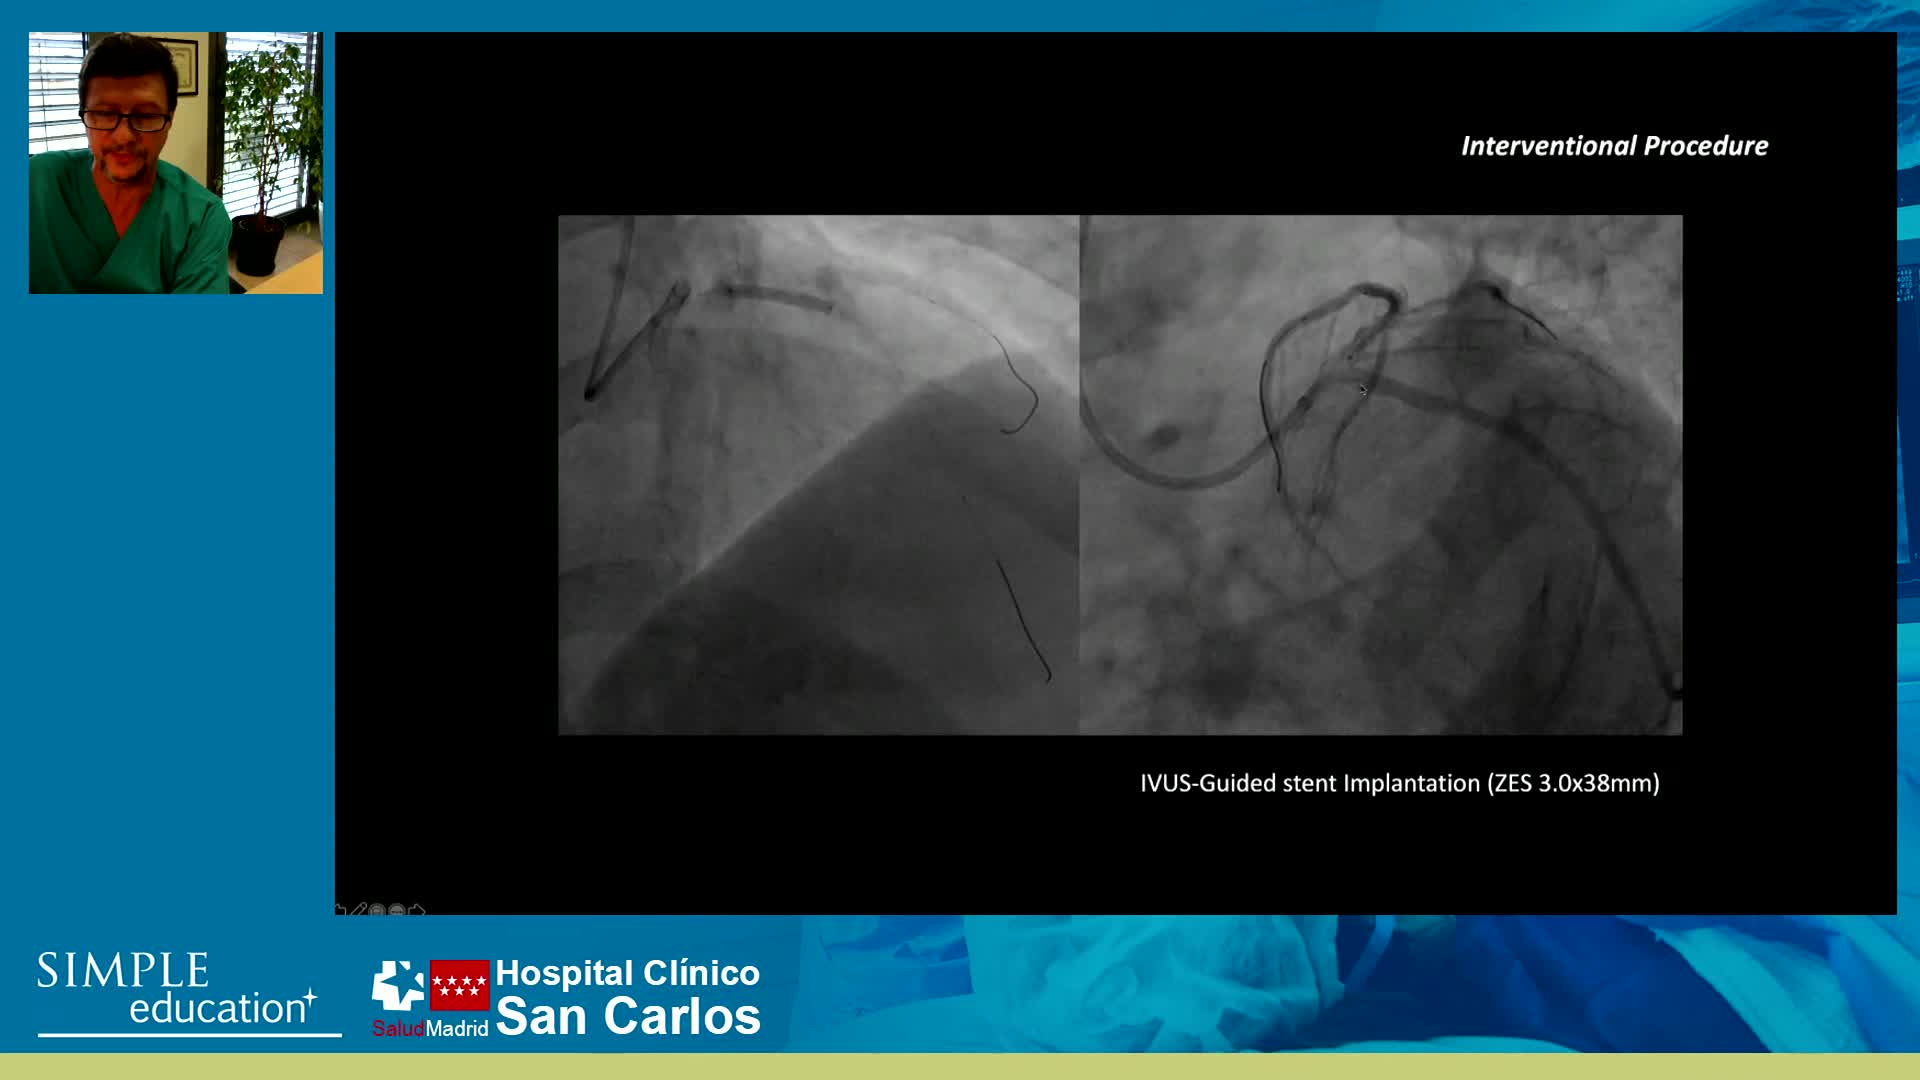

Essential steps for physiology-based PCI planning and guidance - Dr Allen Jeremias

Best practices and personalised medicine in complex PCI - Prof Javier Escaned

How to perform good co-registration measurements using iFR and IVUS - Prof Carlo Di Mario